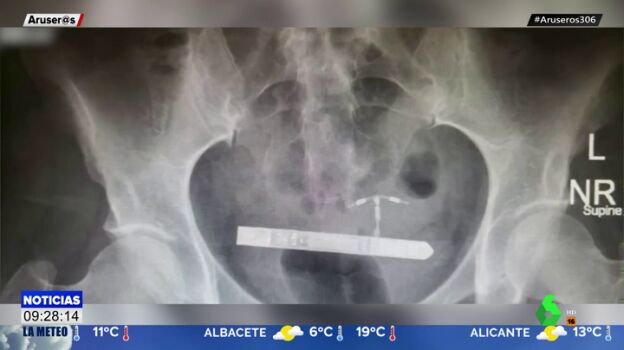

La afectada se introdujo el vibrador de nueve centímetros accidentalmente y llegó hasta la vejiga por la uretra. El ginecólogo que intervino en la operación ha asegurado que "nunca había visto un caso como este en toda su carrera".

El experto ha contado que primero buscaron el objeto en la vagina, pero que gracias a una radiografía descubrieron que se encontraba en la vejiga de la paciente.